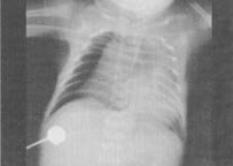

- 单项选择题 患儿,男,生后12天。呼吸困难,哭闹不止。X线检查如图所示,最可能的诊断为()。

- E